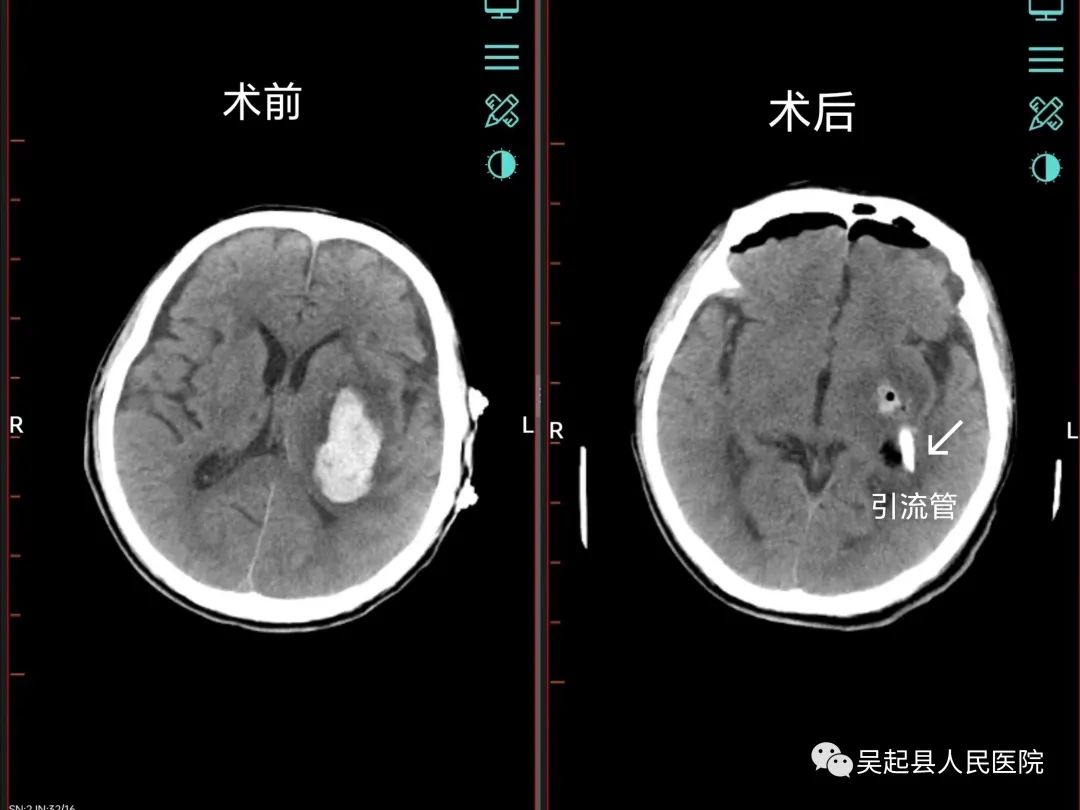

患者男,61岁,主因“突发意识不清伴右侧肢体活动受限3小时”入院,神经外科主治医师任少波为患者急查头颅CT示:左侧基底节区脑出血(出血量约30ml)。患者呈昏睡状,右侧上肢肌力II级、右下肢肌力I级。

大脑是人体的神经中枢,主宰人的各项生理活动,颅内神经血管分布密集,手术医师全神贯注,不敢稍有疏忽,颅骨被精准“打洞”后,血肿位置很快被发现,在内镜辅助下,手术大夫小心翼翼地分离血管,慎之又慎地清除血肿……经历约1小时,一场挽救患者生命、保全患者肢体各项功能的颅脑手术顺利完成,术后患者生命体征平稳,意识转醒。复查CT示:血肿大部分被清除,脑组织压迫情况缓解。(任少波)